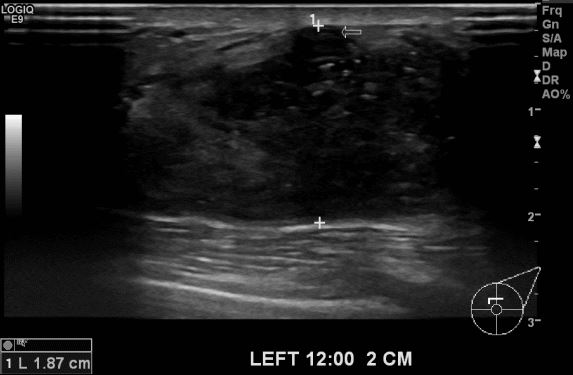

상기환자 좌측 유방에 만져지는 멍울로 내원하신 40대 여성분으로 본원 유방초음파 후

좌측 12시 방향에 만져지는 멍울 조직검사 시행하여 좌측 유관암 진단되었습니다.